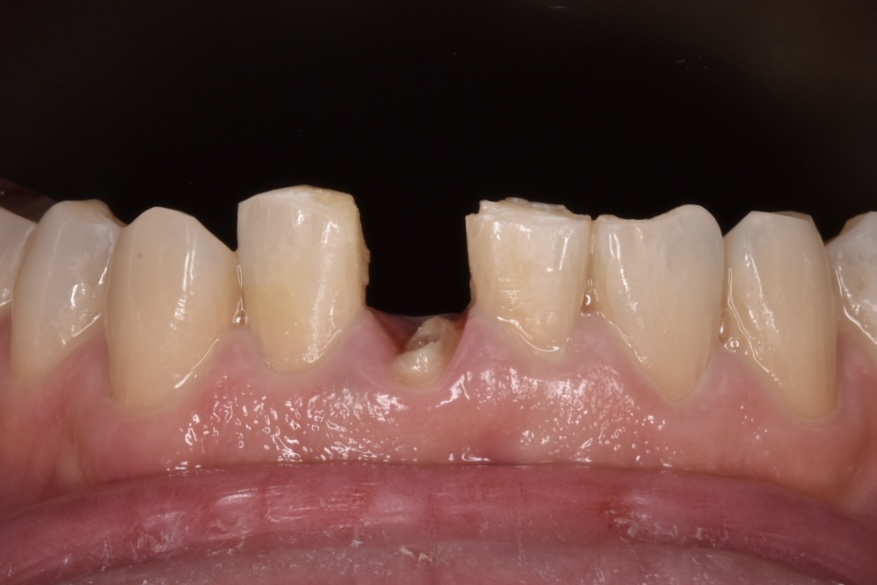

50代男性 下の前歯が東京の歯科で一年ほど前に作られた差し歯で、今回はそれが取れてしまったとご相談いただきました。検査の結果、歯が土台ごと折れていました。折れている場所が歯茎の中の方で折れていて、歯槽骨ギリギリの場所です。

こちらが初診時のレントゲン写真です。歯が水平的に破折していて歯の一部が骨のトップに差し掛かっていることがわかります。

写真の青字:骨のライン

写真ピンク字:歯の断端